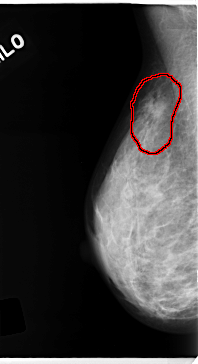

C_0139_1.RIGHT_MLO

FILE: C_0139_1.RIGHT_MLO.OVERLAY

TOTAL_ABNORMALITIES 1

ABNORMALITY 1

LESION_TYPE MASS SHAPE IRREGULAR MARGINS SPICULATED

ASSESSMENT 5

SUBTLETY 4

PATHOLOGY MALIGNANT

TOTAL_OUTLINES 1

BOUNDARY